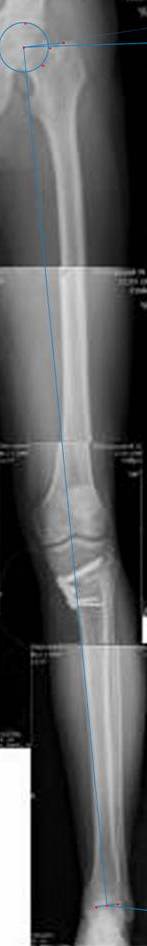

картинки оперированного пациента 40 лет, травма в 2006 году.

оперирован 06.11.2009г - корригирующая остеотомия большеберцовой кости.

Согласен с Вами, эта "скажем" не высокая остеотомия

нужно было выше.....

Я картинку собрал с некоторыми погрешностями, если провести отвес от центра вращения головки бедра до середины голени (на пациенте),то имеется небольшой вальгус (гиперкоррекция)конечно она (гиперкоррекция) не достигает 10 гр, но 5 гр она достигает.

Проблема как сделать рентгеновские снимки а потом их совместить правильно, кто знает как решить этот вопрос. Ведь стандартные размеры рентгенкассет, оснащенные наши стационары отснять всю конечность с трех попыток!

К сожалению, не очень удачный пример. Если верить Р-граммам, имеет место быть дисплазия мыщелков бедренной кости с наклоном суставной линии. Это уже создает сложности получения хороших отдаленных результатов. Кроме того, по классике, необходима гиперкоррекция с созданием вальгуса 7-10 градусов для максимальной разгрузки медиального отдела КС. Если верить укладке, то линия сустава имеет четкий варусный наклон, поэтому результат операции м.б. кратковременным. В этих случаях показана двойная остеотомия бедра и тибии.

Если сделать правильно, то видно, что бедренная кость в порядке, а цель остеотомии (низкой, кстати), не достигнута вовсе.

Сохраняется варус. Для того, чтобы создать вальгусную гиперкоррекцию, не моделируя при этом откровенный Х голени, можно сделать медиализирующую остеотомию.